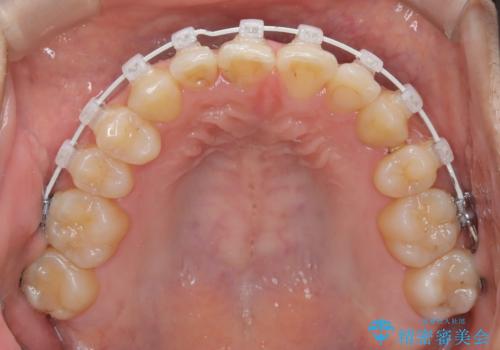

- 患者様は左上の八重歯を気にされて来院されました。八重歯による歯列の乱れだけでなく、翼状捻転(歯がねじれるように生えている状態)も見られました。目立たない矯正を希望されていたため、**インビザライン(マウスピース矯正)**を選択し、左上の小臼歯を抜歯してスペースを作りながら歯を並べる治療計画を立てました。しかし、治療の途中で翼状捻転の改善が十分に進まなかったため、患者様の希望も踏まえ、上顎のみワイヤー矯正に変更することとなりました。

治療開始時はインビザラインを使用し、全体の歯並びを整えながら抜歯スペースを活用して歯を後方へ移動させました。しかし、左上の八重歯のねじれが強く、マウスピースのみでは十分にコントロールできないことが判明。そこで、より細かく歯を動かすために上顎のみワイヤー矯正へ切り替えました。ワイヤー矯正によって翼状捻転も改善し、最終的にバランスの取れた歯並びと噛み合わせを実現。患者様からは「長い治療だったけれど、しっかり整って満足」と嬉しいお言葉をいただきました。